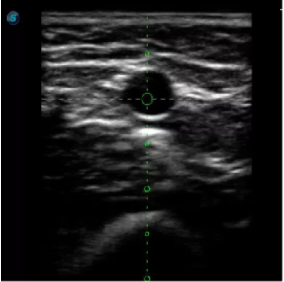

取卵臨床圖

傳統(tǒng)腔內(nèi)探頭采用直柄設(shè)計(jì),在搭配穿刺架使用時(shí),手術(shù)空間小,不易操作;生殖專用的曲柄探頭,探頭柄采用彎曲成角度設(shè)計(jì),可實(shí)現(xiàn)監(jiān)視、取卵兩不誤,搭載穿刺架時(shí),可以清晰顯示穿刺針的進(jìn)針過程、深度和位置,實(shí)時(shí)監(jiān)視取卵全過程,保障取卵操作精準(zhǔn)與安全。